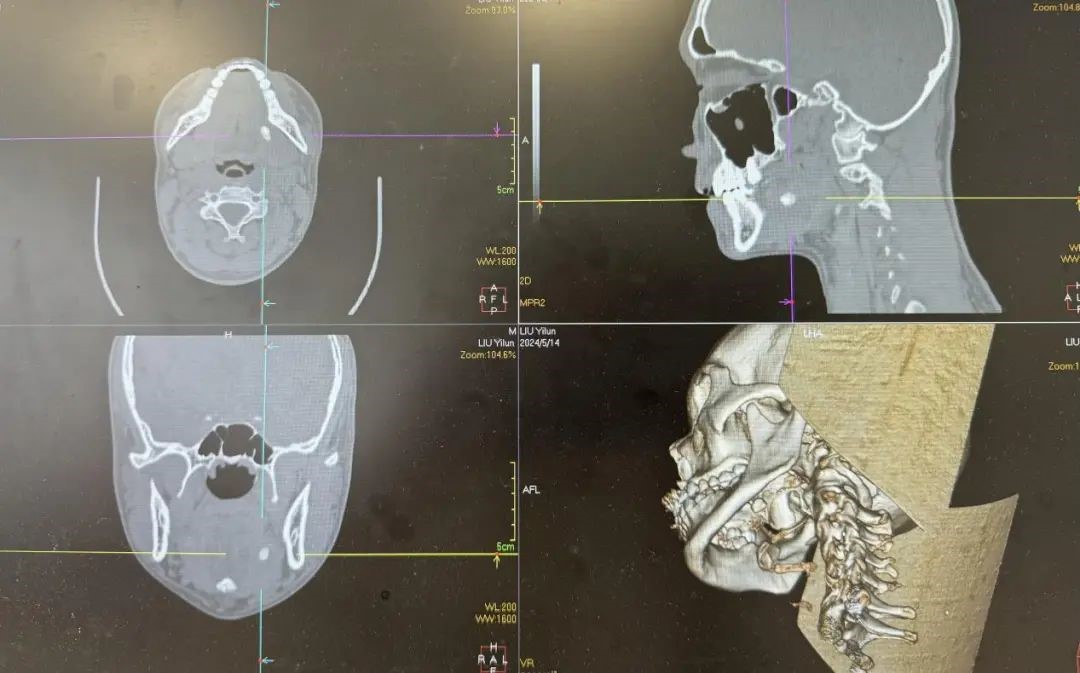

张治军主任概括此病的特点是“颌下肿痛时轻时重,肿块时大时小”,通过下颌区薄层CT平扫检查就可以发现“下颌骨内侧斑点状高密度影”的结石,以此进一步证实临床判断。